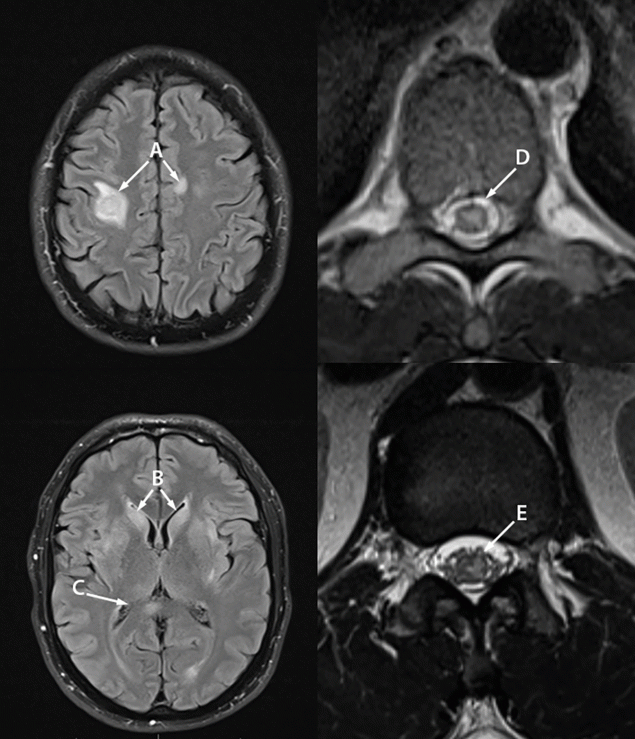

The first case occurred in a previously healthy, presumedly immunocompetent gay man in his 30s in Colorado (patient A). He had no recognized MPXV exposure or recent travel. He was not previously vaccinated against monkeypox or smallpox. In July 2022, he acutely developed fever, chills, and malaise. Three days after symptom onset, an itchy vesiculopustular rash appeared on his face and spread to his extremities and scrotum during the next several days. Swabs of a lesion yielded a positive polymerase chain reaction (PCR) test result for Orthopoxvirus DNA, later confirmed to be MPXV DNA. Nine days after symptom onset, the patient developed progressive left upper and lower extremity weakness and numbness, urinary retention, and intermittent priapism, and was hospitalized. Magnetic resonance imaging (MRI) of the brain showed partially enhancing lesions in the frontal lobes consistent with demyelination as well as nonenhancing lesions of the bilateral basal ganglia, bilateral medial thalami, splenium, and pons (Figure 1). MRI of the spine showed multifocal, longitudinally extensive, partially enhancing lesions of the central thoracic spinal cord and gray matter of the conus medullaris, with a single cervical level of canal stenosis with partial cord compression (presumably chronic and not acute). Cerebrospinal fluid (CSF) analysis demonstrated 155 white blood cells/μL (normal = ≤5) with 60% lymphocytes, 30% monocytes, and 10% neutrophils; 9 red blood cells/μL (normal = 0); glucose 64 mg/dL (normal = 45–80 mg/dL); and protein 273 mg/dL (normal = 15–45 mg/dL). CSF bacterial cultures were negative. CSF herpes simplex virus (HSV) and varicella zoster virus (VZV) PCR test results were negative. No CSF-specific oligoclonal bands (a marker for central nervous system [CNS] inflammation) were present. Serum aquaporin-4 (to evaluate for neuromyelitis optica spectrum disorder [NMOSD]§) and myelin oligodendrocyte glycoprotein (MOG) (to evaluate for MOG antibody–associated disease [MOGAD]¶) antibody test results were negative. Serum HIV serologic and PCR test results were negative. Serum treponemal antibodies and particle agglutination test results were positive; serum rapid plasma reagin (RPR) and CSF venereal disease research laboratory (VDRL) test results were negative, suggesting a past syphilis infection (patient A received a single dose of penicillin after an exposure in 2013). SARS-CoV-2 reverse transcription–PCR nasopharyngeal swab test result was negative, and serum and CSF MPXV PCR test results were negative.

FIGURE 1. Magnetic resonance imaging of the brain, thoracic spine, and conus medullaris of patient A with monkeypox-associated encephalomyelitis showing abnormal T2/fluid attenuated inversion recovery signal in the right frontal and left frontal lobes (A), bilateral basal ganglia (B), bilateral medial thalami and right splenium (C), central thoracic spinal cord (D), and gray matter of the conus medullaris (E) — Colorado, July–August 2022

Photos/Daniel M. Pastula.